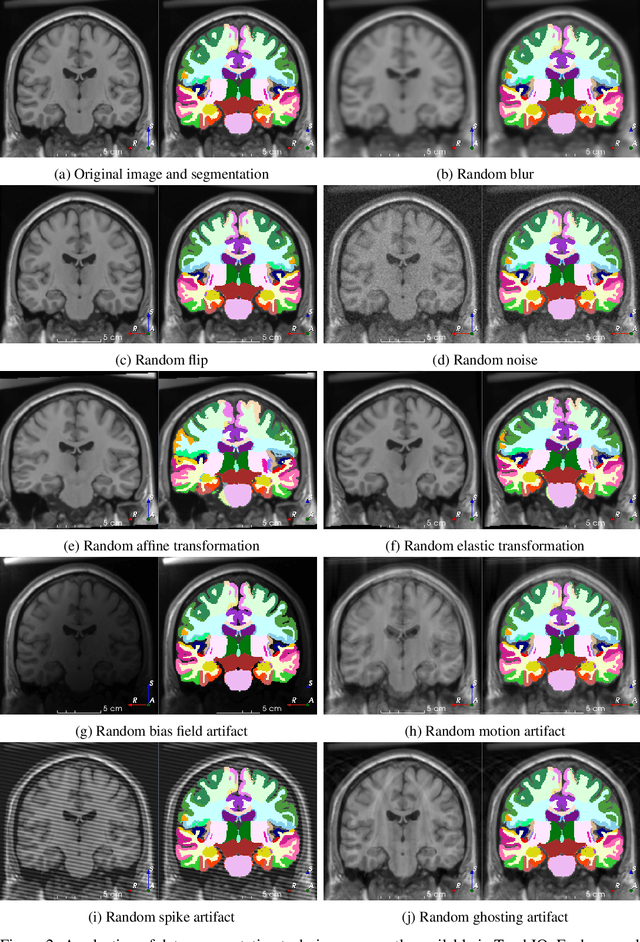

We present TorchIO, an open-source Python library for efficient loading, preprocessing, augmentation and patch-based sampling of medical images for deep learning. It follows the design of PyTorch and relies on standard medical image processing libraries such as SimpleITK or NiBabel to efficiently process large 3D images during the training of convolutional neural networks. We provide multiple generic as well as magnetic-resonance-imaging-specific operations for preprocessing and augmentation of medical images. TorchIO is an open-source project with code, comprehensive examples and extensive documentation shared at https://github.com/fepegar/torchio.